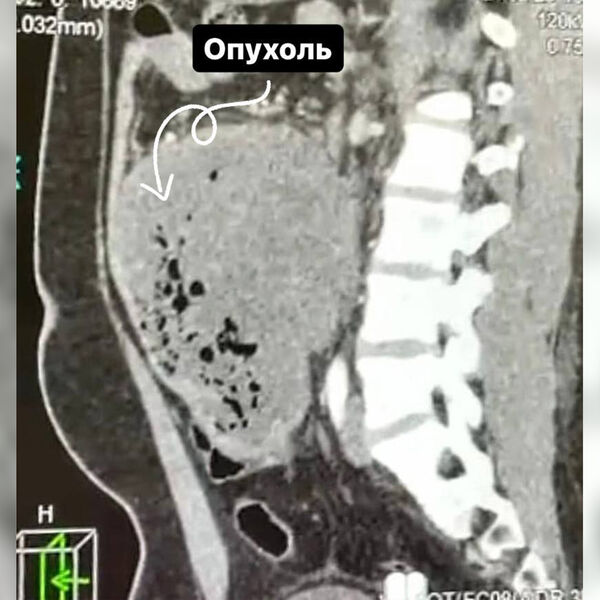

Врачи Долгопрудненской больницы прооперировали 21-летнего пациента со злокачественной опухолью размером 15 см, новообразование мужчина принял за кишечную инфекцию. Об этом сообщает минздрав Московской области.

В ходе обследования в брюшной полости пациента медики обнаружили новообразование. Выяснилось, что неприятные симптомы беспокоили молодого человека в течение месяца, он обращался в частную клинику, но тогда диагностика не выявила никаких отклонений.

«Ситуацию осложняла локализация опухоли, она находилась в труднодоступном для удаления месте — между аортой и нижней полой веной. Под общим наркозом мы удалили 15-сантиметровое образование вместе с участком кишки», — рассказал заведующий хирургическим отделением больницы Сергей Лисин.

Хирургическое вмешательство длилось пять часов, опухоль удалось удалить. Гистологическое исследование показало, что новообразование было злокачественным. Пациент уже выписан на амбулаторное лечение и будет наблюдаться у онколога по месту жительства.